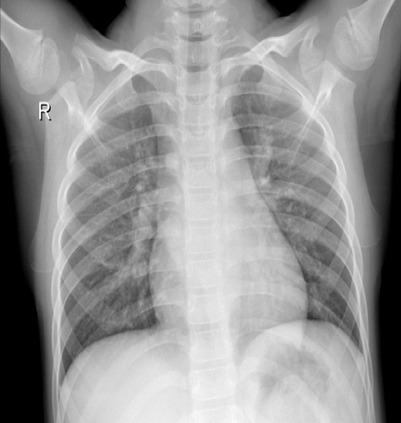

Pneumonia remains a leading cause of morbidity and mortality worldwide. Chest X-ray (CXR) imaging is a fundamental diagnostic tool, but traditional analysis relies on time-intensive expert evaluation. Recently, deep learning has shown immense potential for automating pneumonia detection from CXRs. This paper explores applying neural networks to improve CXR-based pneumonia diagnosis. We developed a novel model fusing Convolution Neural networks (CNN) and Vision Transformer networks via model-level ensembling. Our fusion architecture combines a ResNet34 variant and a Multi-Axis Vision Transformer small model. Both base models are initialized with ImageNet pre-trained weights. The output layers are removed, and features are combined using a flattening layer before final classification. Experiments used the Kaggle pediatric pneumonia dataset containing 1,341 normal and 3,875 pneumonia CXR images. We compared our model against standalone ResNet34, Vision Transformer, and Swin Transformer Tiny baseline models using identical training procedures. Extensive data augmentation, Adam optimization, learning rate warmup, and decay were employed. The fusion model achieved a state-of-the-art accuracy of 94.87%, surpassing the baselines. We also attained excellent sensitivity, specificity, kappa score, and positive predictive value. Confusion matrix analysis confirms fewer misclassifications. The ResNet34 and Vision Transformer combination enables jointly learning robust features from CNNs and Transformer paradigms. This model-level ensemble technique effectively integrates their complementary strengths for enhanced pneumonia classification.